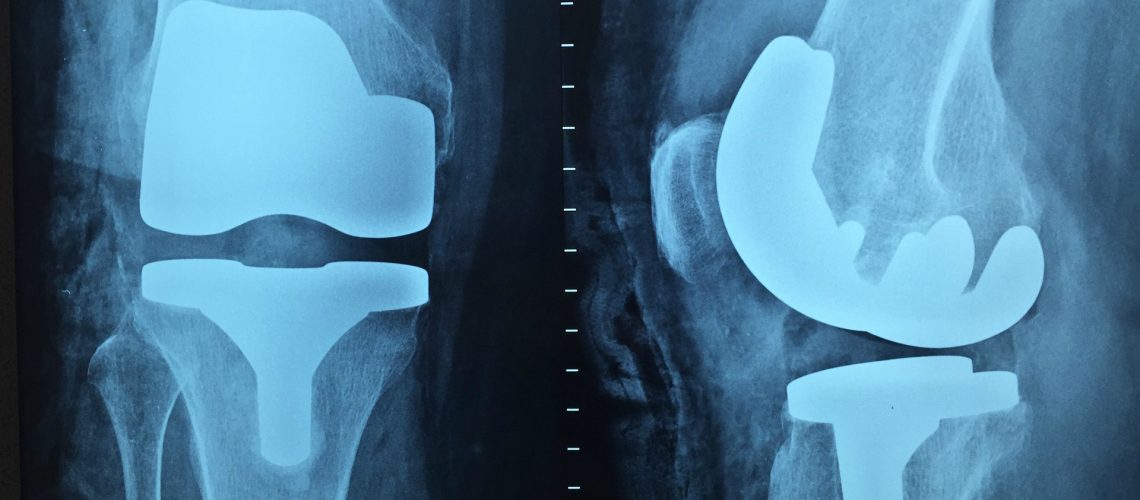

Die meisten Risse heilen nicht, weil es keine Blutzufuhr gibt und so die natürlichen Heilmechanismen nicht einsetzen können. Normalerweise behandelt man so eine Verletzung, indem man den verletzten Teil des Meniskus herausoperiert. Am Anfang funktioniert das noch sehr gut, aber auf lange Sicht funktionieren unsere Knie nicht ohne vollständigen Meniskus. Zum Beispiel kommt es zu Reibung der Knochenenden aneinander und das kann zu frühzeitiger Osteoarthritis führen. Sobald die Arthritis einsetzt, führt sie unaufhaltsam zu chronischem Schmerz und letztlich zu einem Gelenkersatz. Weil Meniskusrisse oft junge, sportliche Menschen betreffen, kann dies viele Jahre der Einschränkung durch Arthritis und einen großen Kostenaufwand für das Gesundheitssystem bedeuten.